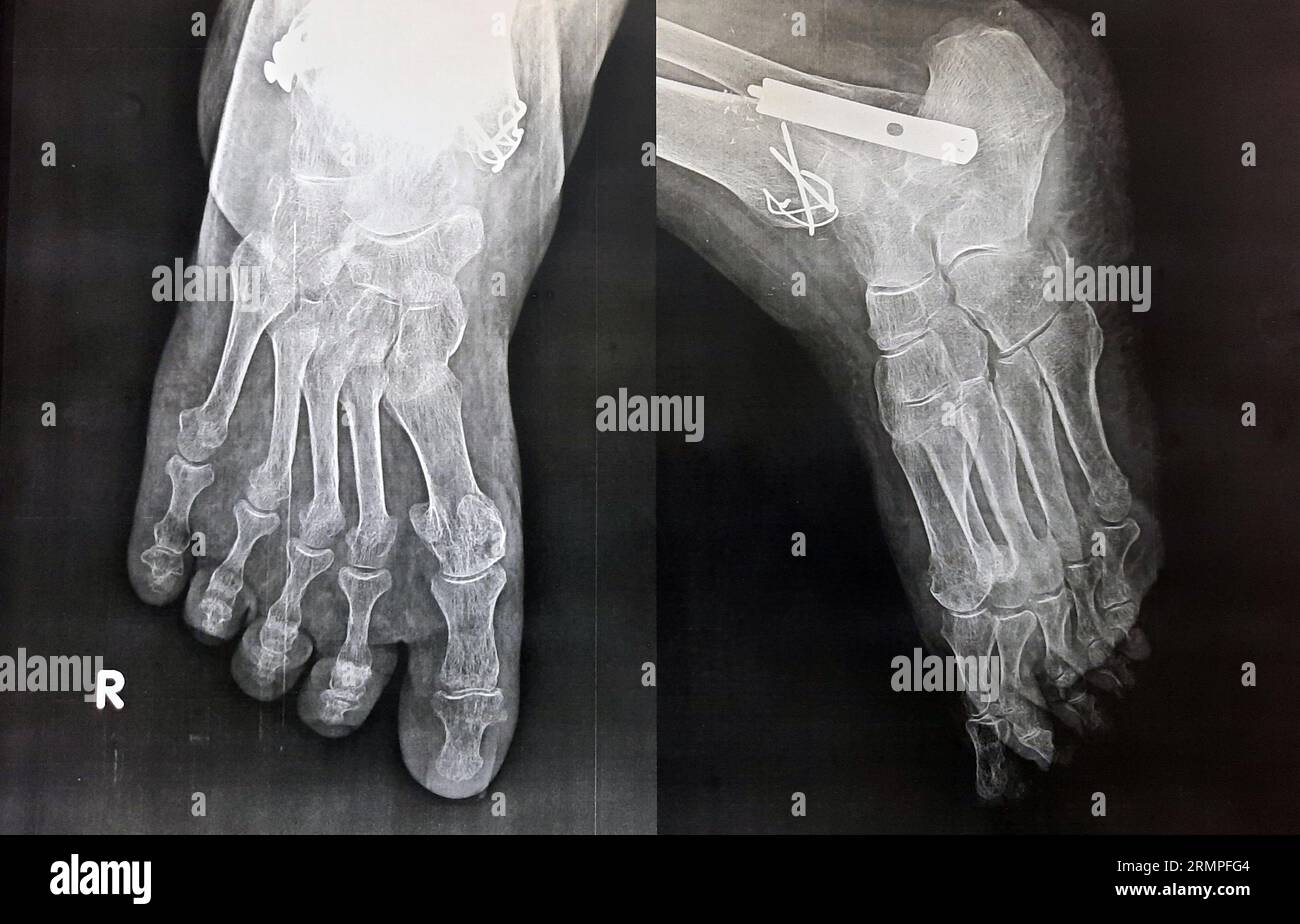

Fissure Fracture X Ray . 'toddler's fracture' = tibial spiral fracture in a toddler. It is necessary when studying the x. Stress fractures of the tibia result from repeated low force trauma. When a person has a bone fracture, one of the first things a person will want to know is how bad it is. Proper description of fractures with knowledge of injury mechanisms, consequent care and complications. It provides an exit route for the chorda tympani from the middle ear to. Transverse, oblique and spiral fractures. The petrotympanic fissure (glaserian fissure) can be visualized on axial and sagittal images (figs. A fissure fracture is noted at the middle third of the right metatarsal bone, more clear on the oblique view (yellow arrow). To determine the severity and treatment/recovery time, doctors will typically perform an. Tibial fractures usually result from high force trauma. Importance of standard radiography of the wrist.

A fissure fracture is noted at the middle third of the right metatarsal bone, more clear on the oblique view (yellow arrow). When a person has a bone fracture, one of the first things a person will want to know is how bad it is. Stress fractures of the tibia result from repeated low force trauma. Tibial fractures usually result from high force trauma. 'toddler's fracture' = tibial spiral fracture in a toddler. It provides an exit route for the chorda tympani from the middle ear to. To determine the severity and treatment/recovery time, doctors will typically perform an. Importance of standard radiography of the wrist. Transverse, oblique and spiral fractures. The petrotympanic fissure (glaserian fissure) can be visualized on axial and sagittal images (figs.

X ray foot showing fracture in Black and White Stock Photos & Images Fissure Fracture X Ray It provides an exit route for the chorda tympani from the middle ear to. It is necessary when studying the x. Tibial fractures usually result from high force trauma. Importance of standard radiography of the wrist. A fissure fracture is noted at the middle third of the right metatarsal bone, more clear on the oblique view (yellow arrow). When a. Fissure Fracture X Ray.